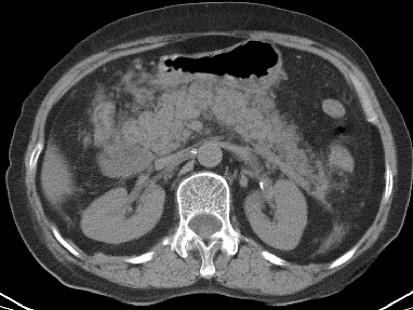

问题 男,30岁,上腹部剧痛,恶心呕吐,压痛反跳痛,血细胞计数升高,血和尿淀粉酶升高,影像表现如图,最可能的诊断是什么 ( )

选项 A、急性胰腺炎 B、慢性胰腺炎 C、胃溃疡穿孔 D、胰腺癌 E、急性肠梗阻

答案 A